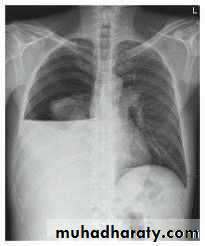

Fall from the 2nd floor